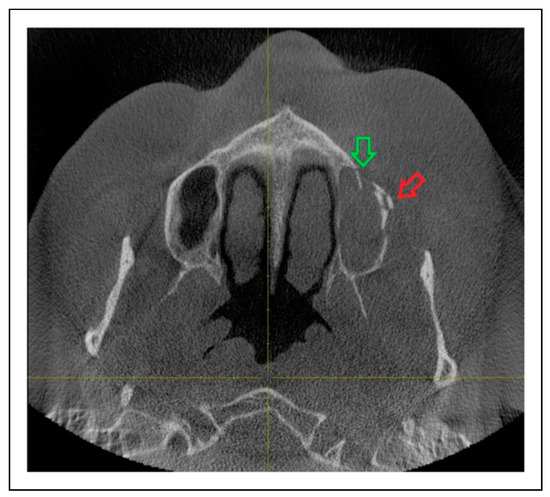

Evaluation of Different Patterns of Zygomaticoorbital Complex Fractures

by Andreas Sakkas, Christel Weiß, Sebastian Pietzka, Frank Wilde, Oliver Christian Thiele and Robert Andreas Mischkowski

Craniomaxillofac. Trauma Reconstr. 2024, 17(2), 92-103; https://doi.org/10.1177/19433875231161906 - 25 Mar 2023

Study Design: Very few studies exist regarding the fracture pattern variability of the zygomaticoorbital (ZMO) complex. The retrospective evaluation of a large series of surgically treated unilateral ZMO fractures would in certain circumstances help intraoperative predictability and define sensitive indicators for open reduction [...] Read more.

Study Design: Very few studies exist regarding the fracture pattern variability of the zygomaticoorbital (ZMO) complex. The retrospective evaluation of a large series of surgically treated unilateral ZMO fractures would in certain circumstances help intraoperative predictability and define sensitive indicators for open reduction and internal fixation. Objective: The aim of this study was to investigate the different fracture patterns after ZMO complex injury regarding the 5 anatomic sutures of the zygoma as well as the concomitance of the paranasal buttress and maxillary sinus wall fracture. Methods: The medical records of all patients with unilateral ZMO fractures who underwent surgical intervention in a single trauma center department between April 2015 and June 2020 were retrospectively reviewed. Demographic and anamnesis data, radiologic findings, and surgical reports were evaluated. According to the preoperative radiologic evaluation, ZMO fractures were classified as unisutural, bisutural, trisutural, tetrasutural, and complete based on the number of zygomatic sutures. The prevalence of various fracture patterns was analyzed. The impact of patient’s age and trauma etiology on the fracture pattern was evaluated using descriptive statistical analysis. Results: The study included 492 patients with unilateral ZMO fractures, with a mean age of 49.93 years (SD = 20.66) and a male:female ratio of 2.23:1. The most affected age group was 19–44 years (41.67%) and tripping falls were the most common etiology (27.24%). Trisutural (57.32%) and unisutural fractures (23.17%) were the most common, followed by tetrasutural (8.94%), bisutural (8.54%), and complete fractures (2.03%). A trisutural fracture involving the zygomaticomaxillary suture, the infraorbital rim, and the zygomaticosphenoidal suture was the most common fracture pattern (52.03%). Most fractures were observed in the zygomaticosphenoidal suture (86.99%), followed by the infraorbital rim (74.59%) and the zygomaticomaxillary suture (68.29%). Fractures of the maxillary sinus wall and the paranasal buttress co-existed in 9.55% and 31.30% of all cases, respectively. No correlation was detected between age and fracture pattern (p = 0.4111). Tripping falls and bicycle accidents significantly influenced the fracture pattern (p < 0.0001). Conclusions: According to the results, knowledge of the fracture pattern variability of the ZMO complex could in certain circumstances designate CT or CBCT as mandatory before operating on ZMO fractures. Consequently, unnecessary incisions could be avoided. The high concomitance of paranasal buttress fracture also suggests its intraoperative surgical exploration. Further studies should correlate the clinical findings with indication for surgery and postoperative outcome for the different fracture patterns described. Full article